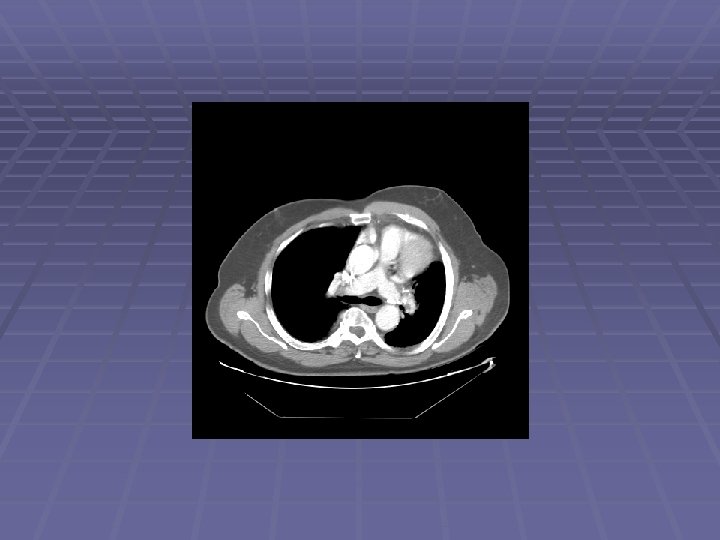

Patient CE 69 y. o. man with h/o non-small cell lung cancer s/p LUL resection in 2006 who is referred after a chest CT showed new mediastinal lymphadenopathy EUS/FNA scheduled to evaluate for recurrent disease

Endosonographic Evaluation EUS Suspicious lymph nodes in the aortopulmonary window, sized 6 -11 mm Suspicious lymph nodes in the subcarinal space, sized 6 -12 mm FNA performed